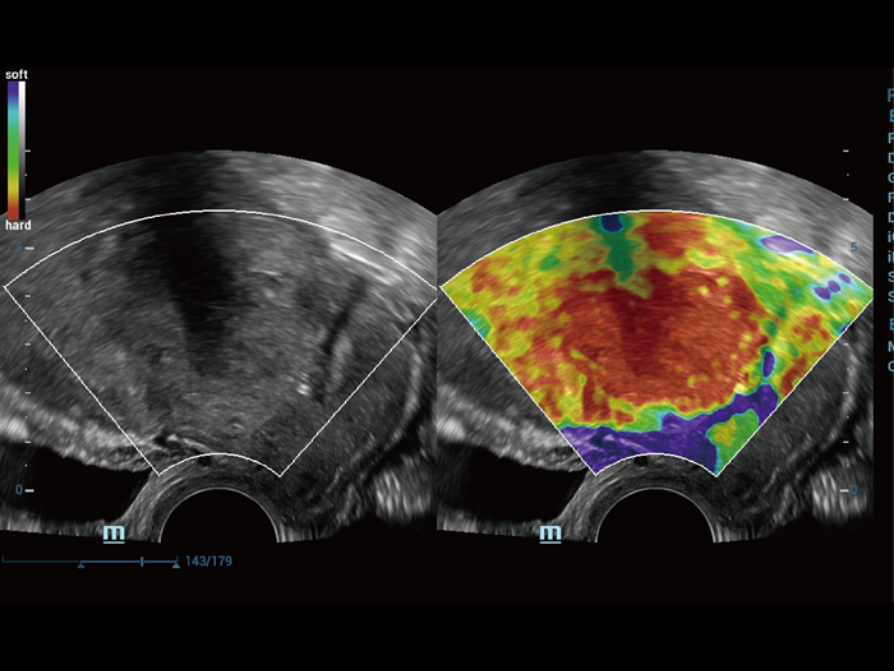

Natural touch Elastography provides multiple relative strain and stiffness parameters of breast, cervix, uterus and ovary lesion. With excellent sensitivity and stability, it provides further diagnostic information for more challenging demands.